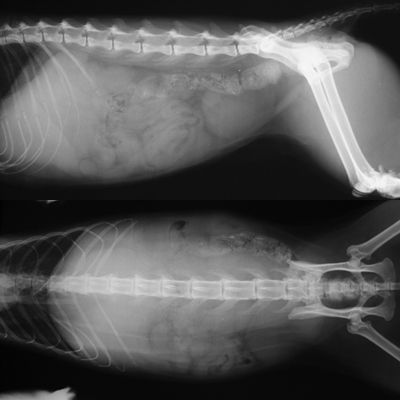

- 編號: 3177

主題: 失蹤多日之爆瘦橘貓 申請者姓名: 陳露露 花色: 申請日期: 2013-10-31 08:18:09 申請者部落格: 申請者臉書網址: 所在縣市/合作醫院: 高雄市/樂生動物醫院 治療費用: 12300元 需求人數: 14人 已結案 (2014-01-10 17:58:09) 報名人員: 布蘭卡小姐(已付款)、邱小咪(已付款)、Bubu Wang(已付款)、Cindy Chen(已付款)、Cindy Chen x2(已付款)、張鋅祺(已付款)、有貓真好(已付款)、Cathy Kao(已付款)、peggy(已付款)、陳湘淇(已付款)、lavinia x3(已付款)、 候補人員: 動物病情說明: 此貓為志工餵養已久之浪貓

經送醫後醫生表示

橘子有發燒及脫水,黃疸的現象,

初步血檢有貓愛滋,

且白血球偏低及肝指數過高的現象,

可能與貓愛滋發病或肝細胞受損有相關性,

初步先點滴及給藥治療,再做評估及檢查,

看改善情況後,再做調整

經一段時間的醫療後,橘子終於病癒出院